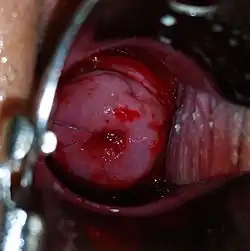

Procedure

During the insertion procedure, health care providers use a speculum to find the cervix (the opening to the uterus), pinch the cervix to stabilize it open with a tenaculum,[74] and then use an insertion device to place the IUD in the uterus. The insertion device goes through the cervix. The procedure itself, if uncomplicated, should take no more than five to ten minutes.[75]

A suction cervical stabilizer can be used in place of the standard tenaculum to hold the cervix open during the IUD insertion procedure.[76] Suction cervical stabilizers, such as The Carevix™ Suction Cervical Stabilizer,[77] may reduce pain associated with the insertion procedure.[78]